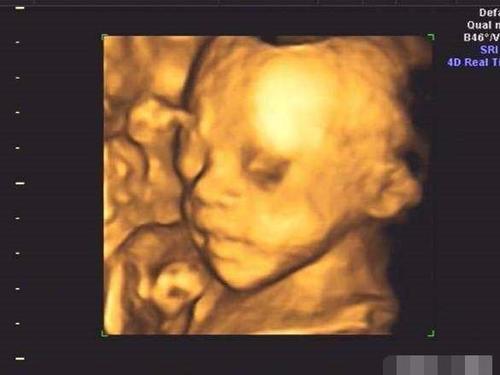

24周四维,24周四维图片胎儿全图

24周四维图片胎儿全图

胎儿24周四维彩超图

四维彩超

女宝四维

24周四维男孩生殖图片

男宝四维彩超图

孕24周男宝图

宝宝四维照片

确认女宝四维图

四维确认女宝b超图

四维彩超男孩清晰图